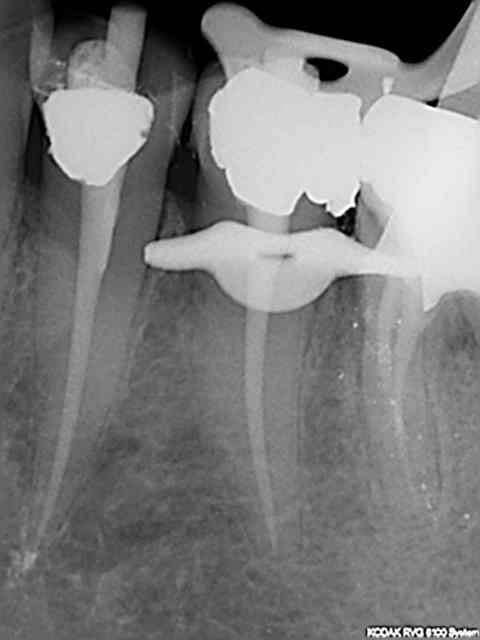

J'ai fait une reprise de TR sur 27 en novembre dernier ; digue, javel, NiTi, pour un bon résultat radio.

Aucun problème de symptomatologie, radio argentique et numérique OK, et découverte forfuite d'un kyste énorme sur la racine vestibulaire de cette dent lors d'un scan pour implant en place de 37.

Si-si il a raison les radios exposées en nombre font toutes preuve d'un traitement parfait et ce en un temps plus que raisonnable.